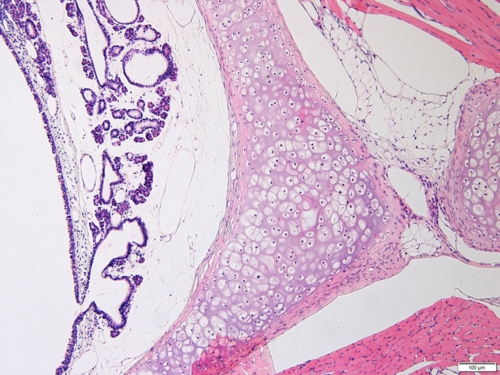

喉頭(ラット) Larynx ( rat )

厚さ5 µm パラフィン切片のヘマトキシリン・エオジン染色光学顕微鏡画像

Light microscopic image of 5 µm-thin paraffin section with hematoxylin & eosin staining

喉頭がつぶれないように周囲を取り囲む硝子軟骨の構造が捉えられます